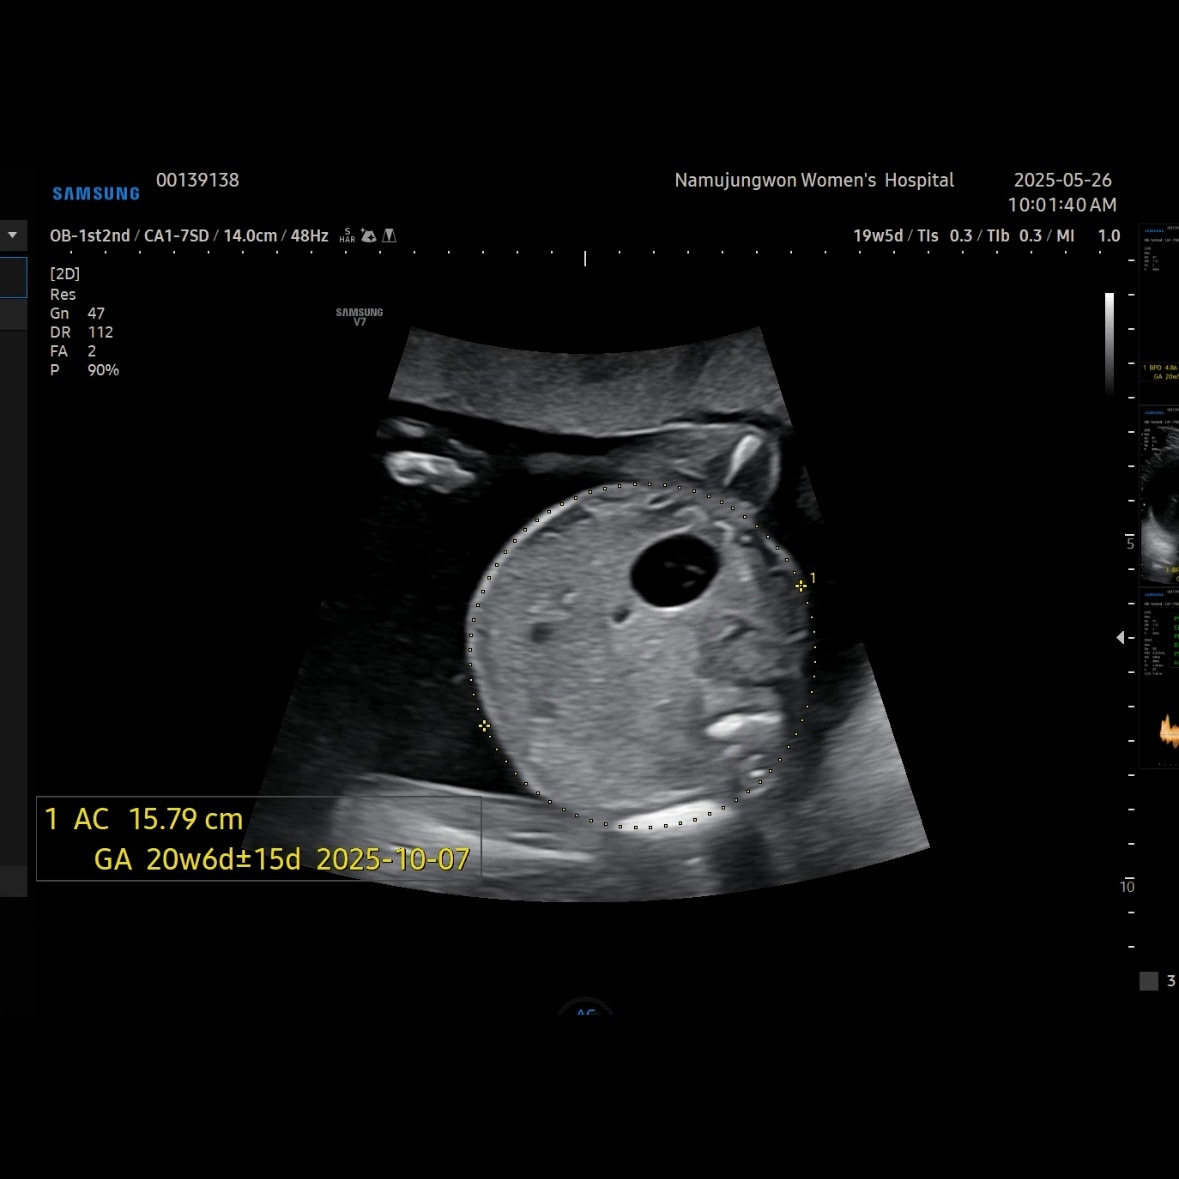

유민이 19주 5일 차에 보러 간 초음파

초음파를 보면 머리둘레, 배둘레, 허벅지 뼈길이를 꼭 재보는 데 유민이는 갈 때마다 1주 정도씩 평균보다 크게 측정된다. 1-2주 크기차이는 의미 없다고 괜찮다고 했다.